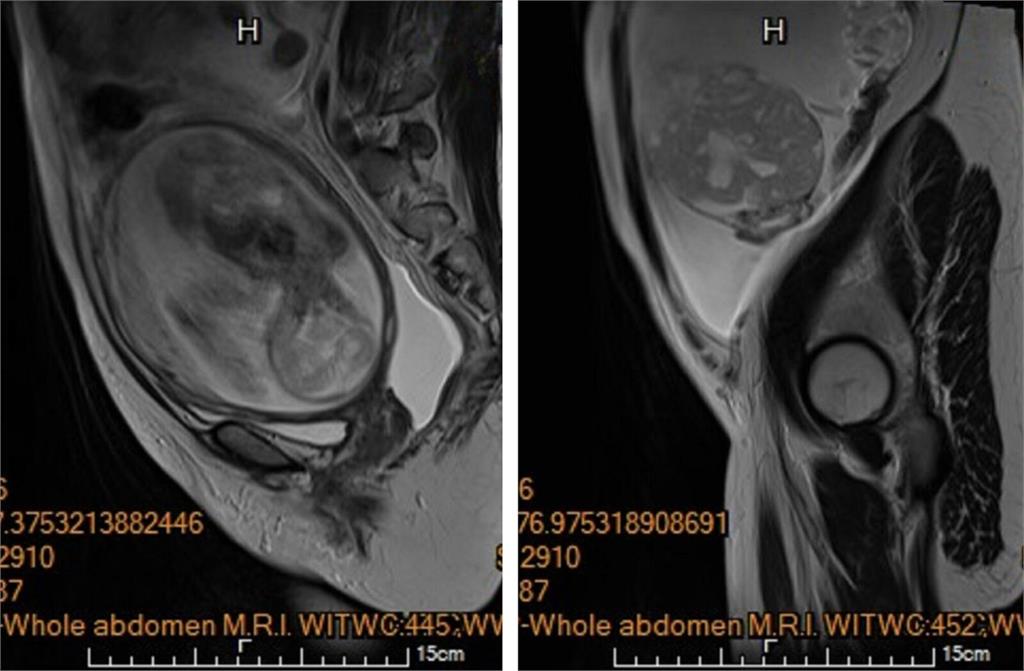

懷孕5個月,卻發現跟孩子一起長大的還有腫瘤!今年30歲、懷第一胎的李小姐就面臨這樣的危急狀況,產檢意外發現腹腔內積滿大量腹水,左側下腹部還驚見一個15公分大小、邊界模糊、結構複雜的卵巢腫瘤,惡性風險極高,可能得一次失去子宮跟胎兒,一度讓她萬念俱灰,所幸馬偕醫院醫療團隊儘速安排切除腫瘤,盡最大努力持續讓腹中胎兒長大到足月,自然產下2808公克的健康女寶寶。

陳楨瑞說,李小姐手術前,血液檢查發現異常超高的抗穆勒氏荷爾蒙(AMH)指數>22.5,而正常育齡女性數值介於2至5,已經強烈懷疑為卵巢顆粒細胞癌,馬上採傳統開腹手術,在不造成腫瘤破裂的情況下,順利切除包含惡性腫瘤的左側卵巢輸卵管,並取部分大網膜組織進行病理檢驗,幸運的是,手術時於腹腔內並沒有發現腫瘤擴散或轉移跡象,子宮與右側卵巢輸卵順利保留,子宮內胎兒也未受到手術影響。

陳楨瑞指出,病理報告雖證實為卵巢癌,但是屬於低度惡性的「幼年型顆粒細胞瘤」,免於後續在懷孕期間接受化學治療。李小姐術後恢復極佳,先前因腹水引起的腹脹、呼吸困難等症狀也完全消退,孕程得以順利延續,在妊娠38週,自然產下2808公克的健康女寶寶,產後門診追蹤無腫瘤復發跡象,寶寶也十分健康。